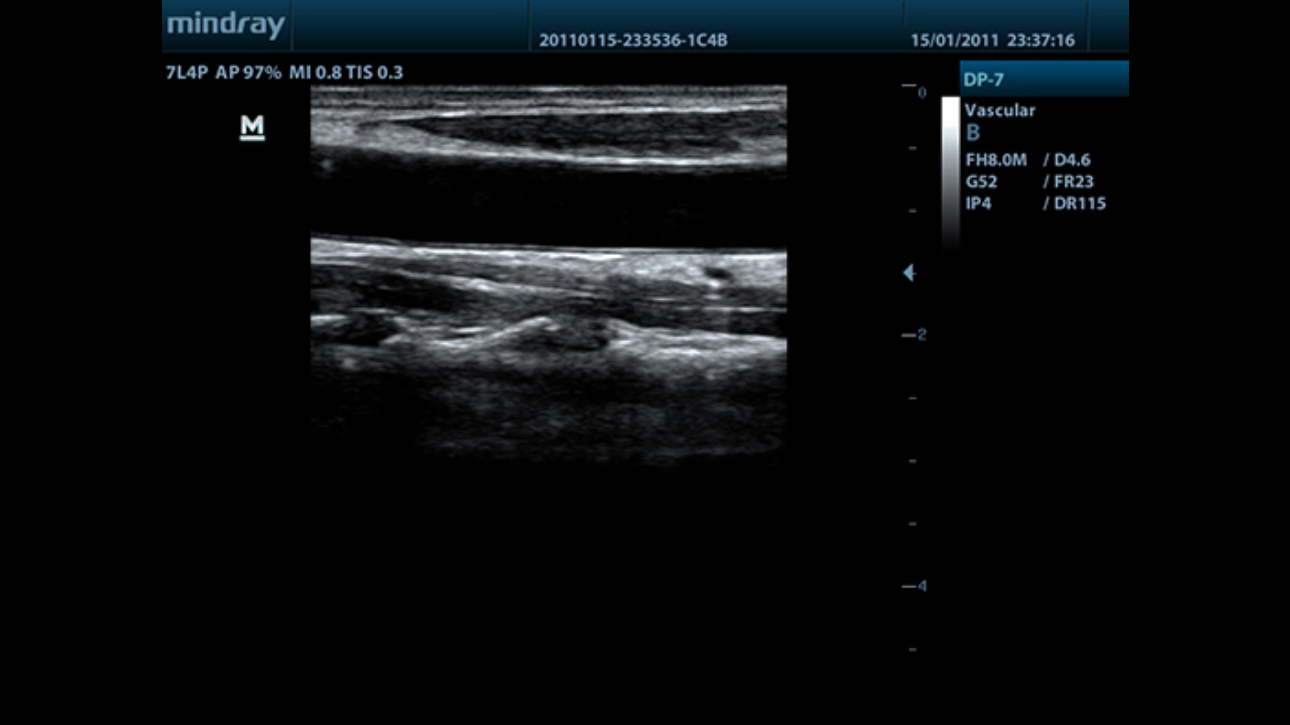

DP-7

Overview

MindrayŌĆÖs new generation of black & white ultrasound system, DP-7, offers a combination of good image quality, highly efficient workflow and a slim design for your varied requirements. Based on physical channels higher than most similar systems, DP-7 is compatible with a wide selection of newly designed ultra-wide band probes, making it suitable for various clinical settings.

Performance

PSHI??(Phase Shift Harmonic Imaging)

Purified Harmonic Imaging for better contrast resolution providing clearer images with excellent resolution and less noise.

iBeam?

Permits use of multiple scanned angles to form a single image, resulting in enhanced contrast resolution and improved visualization.

iClear?

Gain improved image quality based on auto structure detection.

┬Ę Sharper & Continuous Edges

┬Ę Smooth Uniform Tissues

┬Ę Cleaner ŌĆśno echo areasŌĆÖ

Multiple Beam Formation

Maximum 4 times tasking for one transmitted beam, resulting in excellent time resolution and higher frame rate.